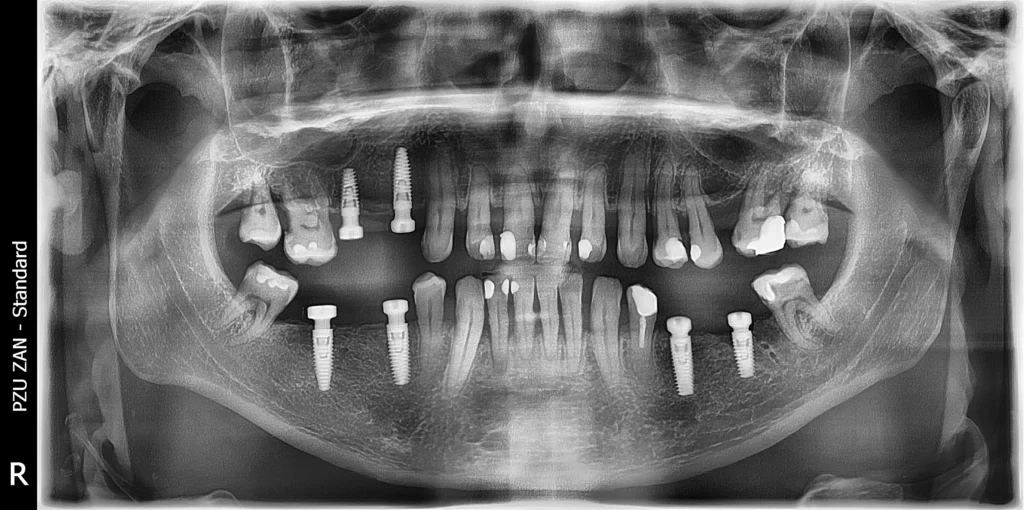

After a thorough clinical examination and detailed 3D imaging, we developed a carefully structured treatment plan that combined dental implants with the preservation of his natural teeth wherever possible. Our goal was not only to restore function and aesthetics, but also to ensure a comfortable and stress-free experience for the patient.

Using advanced computer-aided surgical guides, we precisely placed six dental implants. At the same time, we extracted the teeth that could not be saved and immediately provided the patient with temporary teeth, allowing him to maintain function and appearance throughout the healing process.